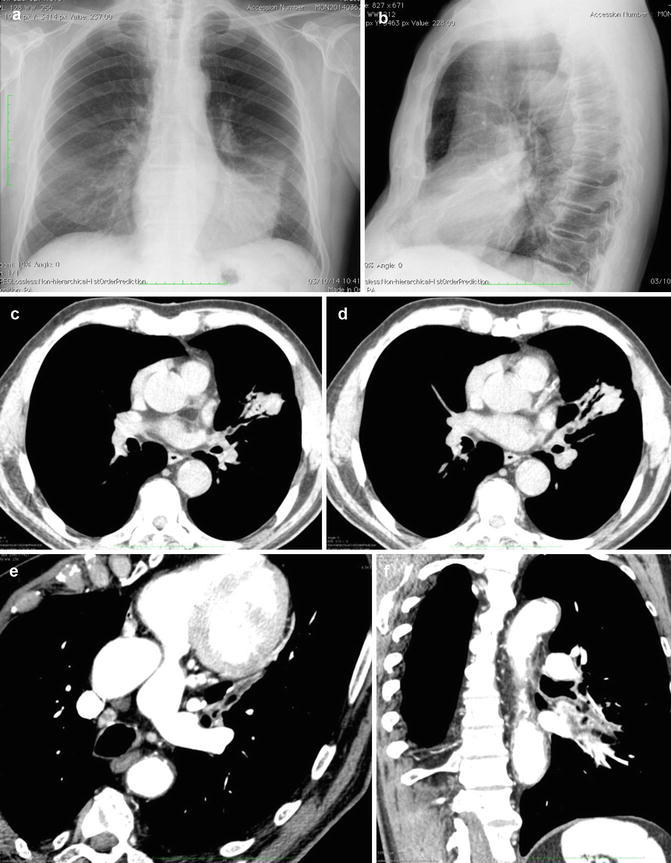

Fig. 13.

Chest radiography findings in bronchiectasis. (a) In both upper lobes, CXR shows parallel tubular opacities due to partial fluid-filled airways. (b) The signet ring sign (arrow), a dilated bronchus immediately adjacent to a smaller companion pulmonary artery. (c, d) Integrated imaging (CXR and MDCT) shows upper right lobe ring opacities or cystic spaces, sometimes with air–fluid levels (demilunes)

Fig. 14.

Chest radiography findings in acute exacerbation of bronchiectasis. (a) CXR of a parahilar “gloved finger,” typically seen in patients with mucoid impaction of the airways due to ABPA (arrows). (b) Bilateral focal areas of subsegmental collapse and patchy peribronchial consolidation from mucous plugging (arrows). (c) Large consolidations in both mid-lower lungs are an unusual feature of an infective exacerbation of bronchiectasis. (d) CXR shows diffuse lung nodular-like pattern from mucous filled airways (P. aeruginosa)